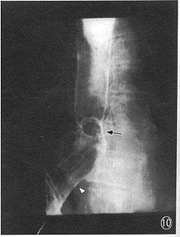

6.整体食管松弛扩张:食管呈囊袋状,无或仅有微弱蠕动,LES经常开放,极少闭合,胃内容可随体位自由流至食管,为弛缓症的典型表现。弛缓症原为小儿的罕见病,但笔者发现2例成年病人,1例在肿瘤化疗后(图10),1例为硬皮病患者,其食管表现均如上述,LES压力测定低于正常。此2例患者病前曾作食管造影未见异常。

图10 十二指肠癌化疗后,食管呈弛缓症表现,无蠕动、无收缩,LES亦呈扩张状态;伴有裂孔疝(△)。食管与胃黏膜连接处的贲门(指B环或Z线)环状结构影(↑)清楚显示